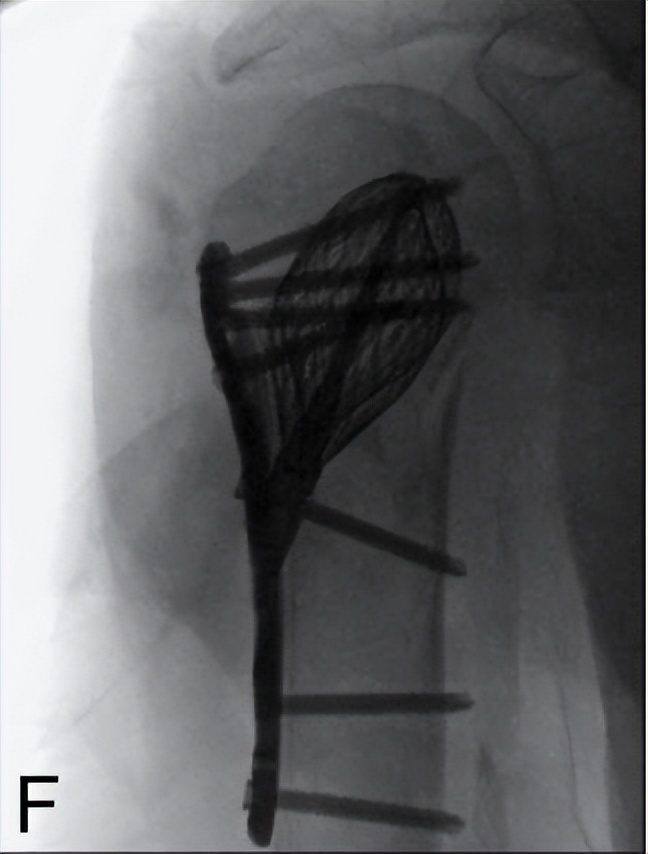

2.2 非典型股骨骨折:Yoon YC[48]介绍了通过矫正截骨、髓内钉可附加钢板强化固定治疗前外侧弓角度增加引起的不完全非典型股骨骨折治疗方法(图7)。20例股骨中有19例在平均24.9周内实现了初次骨愈合。2例延迟愈合,分别于36周和40周愈合。侧弯角度、前弯角度和股骨远端外侧角术后均有显著改善。1例骨不连,附加钢板强化、未植骨后愈合。

图7 Yoon YC研究:骨扫描见不全骨折,截骨后髓内钉固定,6个月后骨折愈合